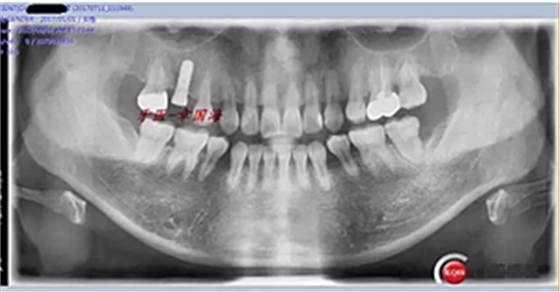

種植后圖片:

完成。

附另外一種植前后圖: